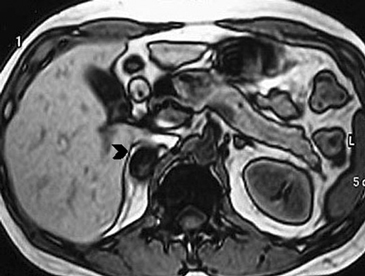

Las lesiones de mayor tamaño con frecuencia presentan componentes quísticos debido a necrosis central o hemorragia antigua (Figura 25 a, b, c y d).

Figura 25. Feocromocitoma quístico. Cortes axiales de resonancia magnética (a) ponderado en T2 secuencia HASTE y (b) ponderado en T1 con saturación grasa y uso de contraste ev. Se identifica una lesión sólido-quística suprarrenal derecha, marcadamente hiperintensa en secuencias ponderadas en T2 y con significativo refuerzo de sus septos con el uso de contraste. Otro caso (c) y (d) cortes axiales de TC donde se demuestra una lesión suprarrenal izquierda (flecha), que también presenta áreas hipodensas centrales determinadas por focos de degeneración quística.